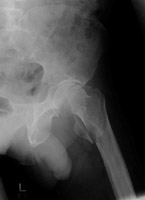

- Click on the image for a larger versionAAP radiograph of the left hip. This demonstrates an intertrochanteric fracture of the left femur.